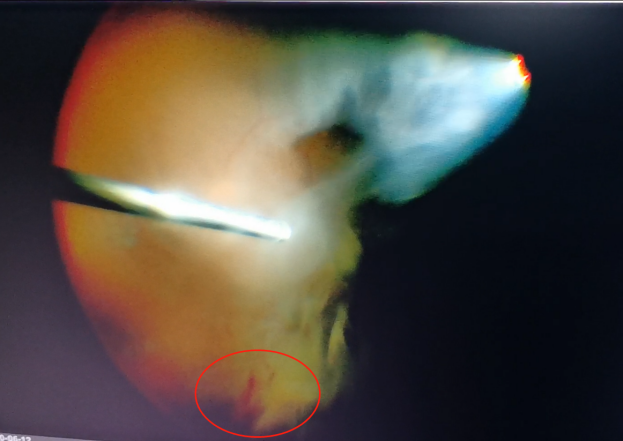

(左為玻璃體切割術(shù)中,明顯可見有積血;右為激光治療后的眼底)

手術(shù)中,醫(yī)生們先后為程先生行白內(nèi)障超聲乳化術(shù)及后入路玻璃體切割術(shù),并置入人工晶體。手術(shù)僅用半個小時便順利完成。